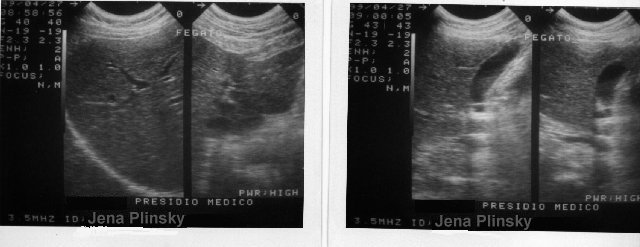

ecco qua il fegato del plinsky. la sorpresa � che non c'� traccia di cirrosi... |